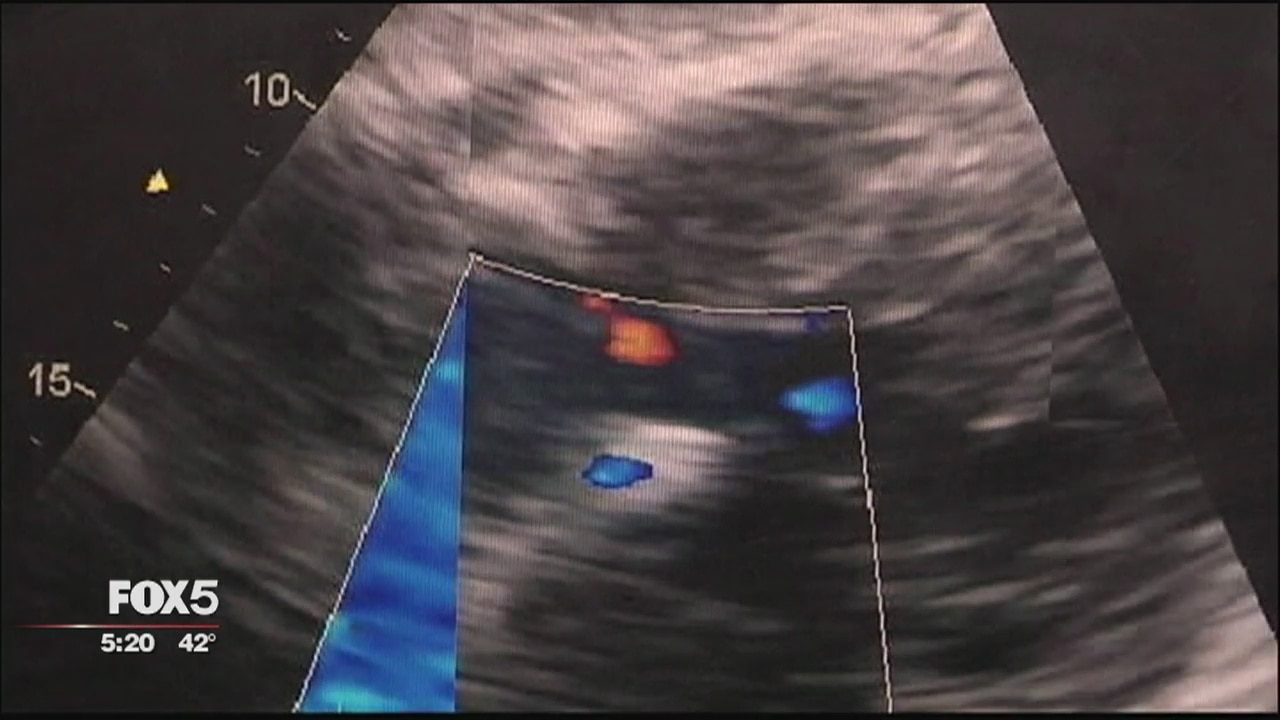

Doctors say symptoms of heart disease are different in women than men. Over 6 million women in the U.S. are diagnosed with the disease. Two-thirds of them may not be aware they're experiencing a heart attack.